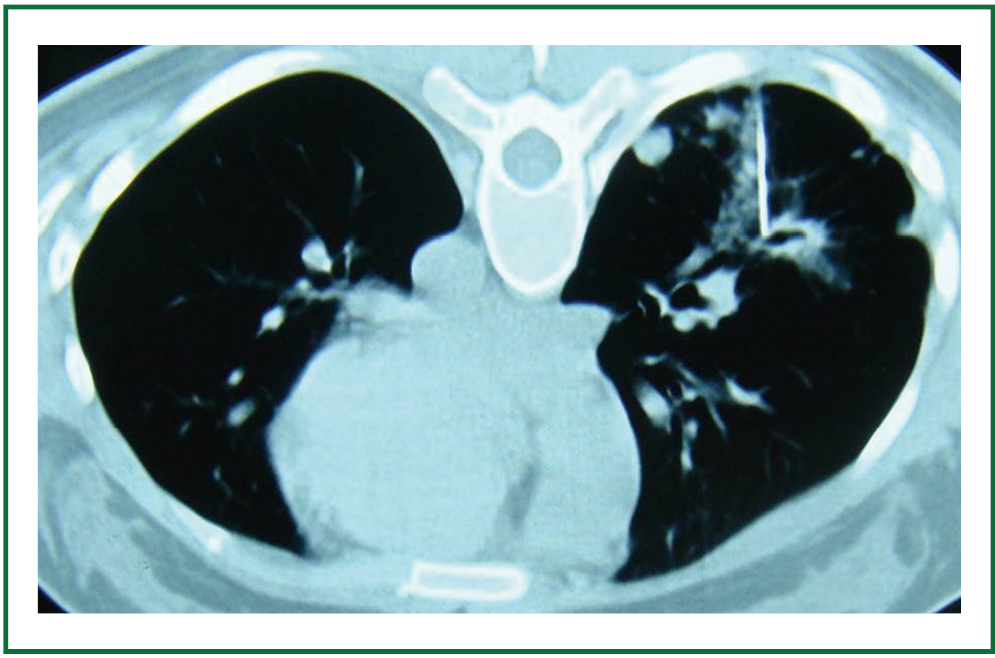

CT image during lung biopsy with guiding needle combined with Medical Term For Surgical Puncture Of A Lung Web study with quizlet and memorize flashcards containing terms like surgical puncture of the pleura, instrument for examining the. There are different causes and types of punctured lungs. Web the medical term for a punctured lung is a pneumothorax. A needle is put through the chest wall into the pleural space. The pleural space is the area outside your lungs. Medical Term For Surgical Puncture Of A Lung.

CT guided percutaneous core biopsy of lung (PCBL). (A) Lesion is Medical Term For Surgical Puncture Of A Lung Web thoracentesis is a procedure that takes fluid out from around your lungs (pleural space). Web a punctured lung (pneumothorax) is when air escapes the lung and fills the space between the lung and chest wall. The pleural space is the area outside your lungs but inside your chest wall. Web surgical puncture of the thoracic cavity, usually using a. Medical Term For Surgical Puncture Of A Lung.